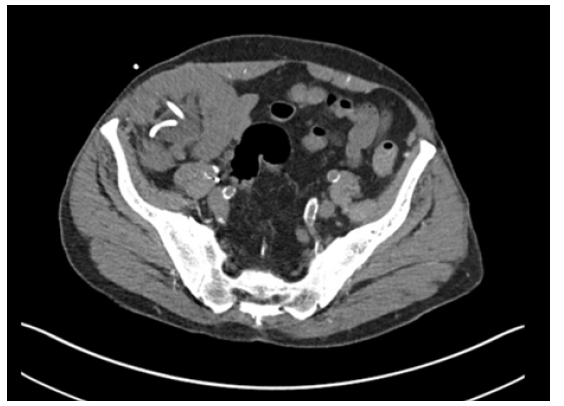

Computed Tomography (CT) upon admission demonstrated the transplanted ureter coursing into the right inguinal hernia resulting in obstruction with marked transplant hydroureteronephrosis (Figure 1). Both urine and blood cultures were found to be positive for Proteus mirabilis for which he was subsequently treated. Ultrasound of the transplanted kidney the following day continued to demonstrate hydroureteronephrosis with no change from prior CT. Fortunately, transplant vasculature was found to be patent with only mild tapered narrowing at the donor renal vein anastomosis (Figure 2). Interventional radiology was consulted for the placement of a percutaneous nephroureteral catheter that was successfully placed on hospital day 1.

Figure 1: CT imaging demonstrating obstruction of the ureter secondary to incarcerated right inguinal hernia.